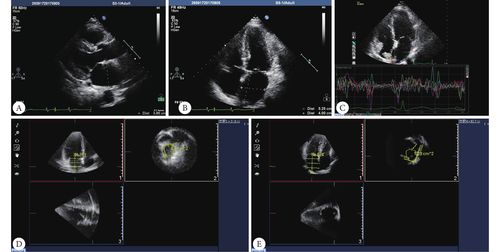

2经胸二维超声心动图